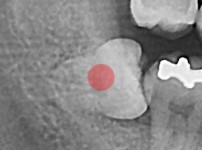

严重龋坏的智齿